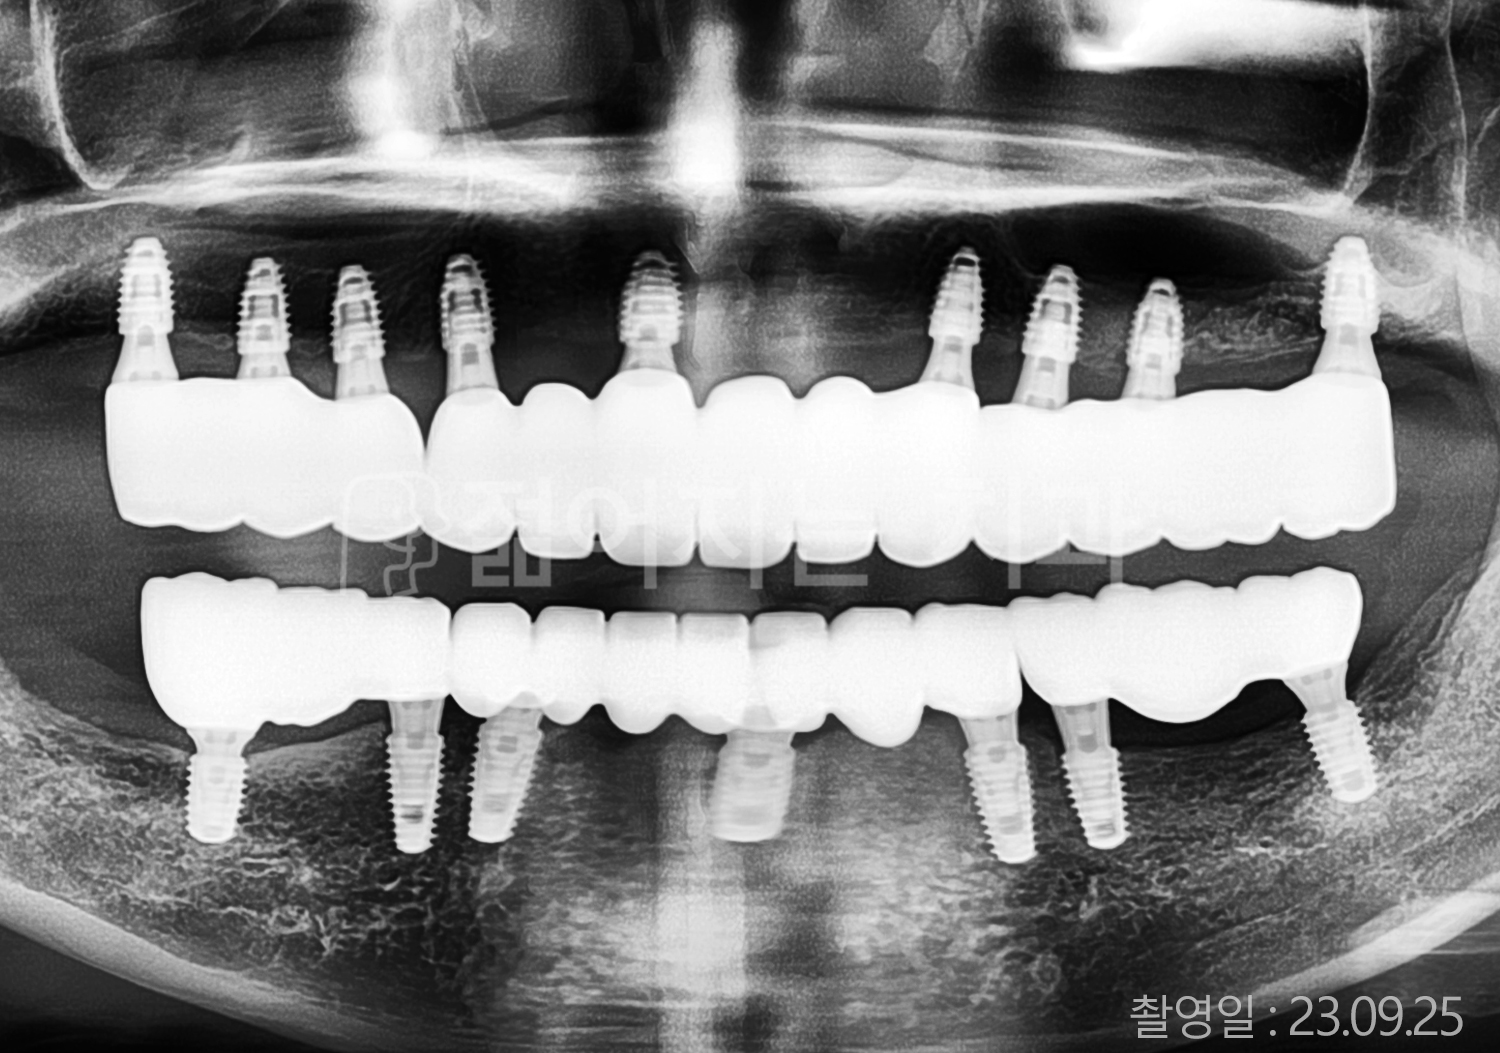

• 50대 고혈압, 당뇨, 고지혈증 전체치아 10개 이상 임플란트

• 60대 골다골증, 간경화 전체치아 10개 이상 임플란트

• 60대 고혈압, 고지혈증 전체치아 10개 이상 임플란트

• 50대 고혈압, 당뇨 전체치아 10개 이상 임플란트

• 60대 고혈압 전체치아 10개 이상 임플란트

• 60대 전체치아 10개 이상 임플란트

• 60대 고지혈증 전체치아 10개 이상 임플란트

• 40대 전체치아 10개 이상 임플란트

• 70대 전체치아 10개 이상 임플란트